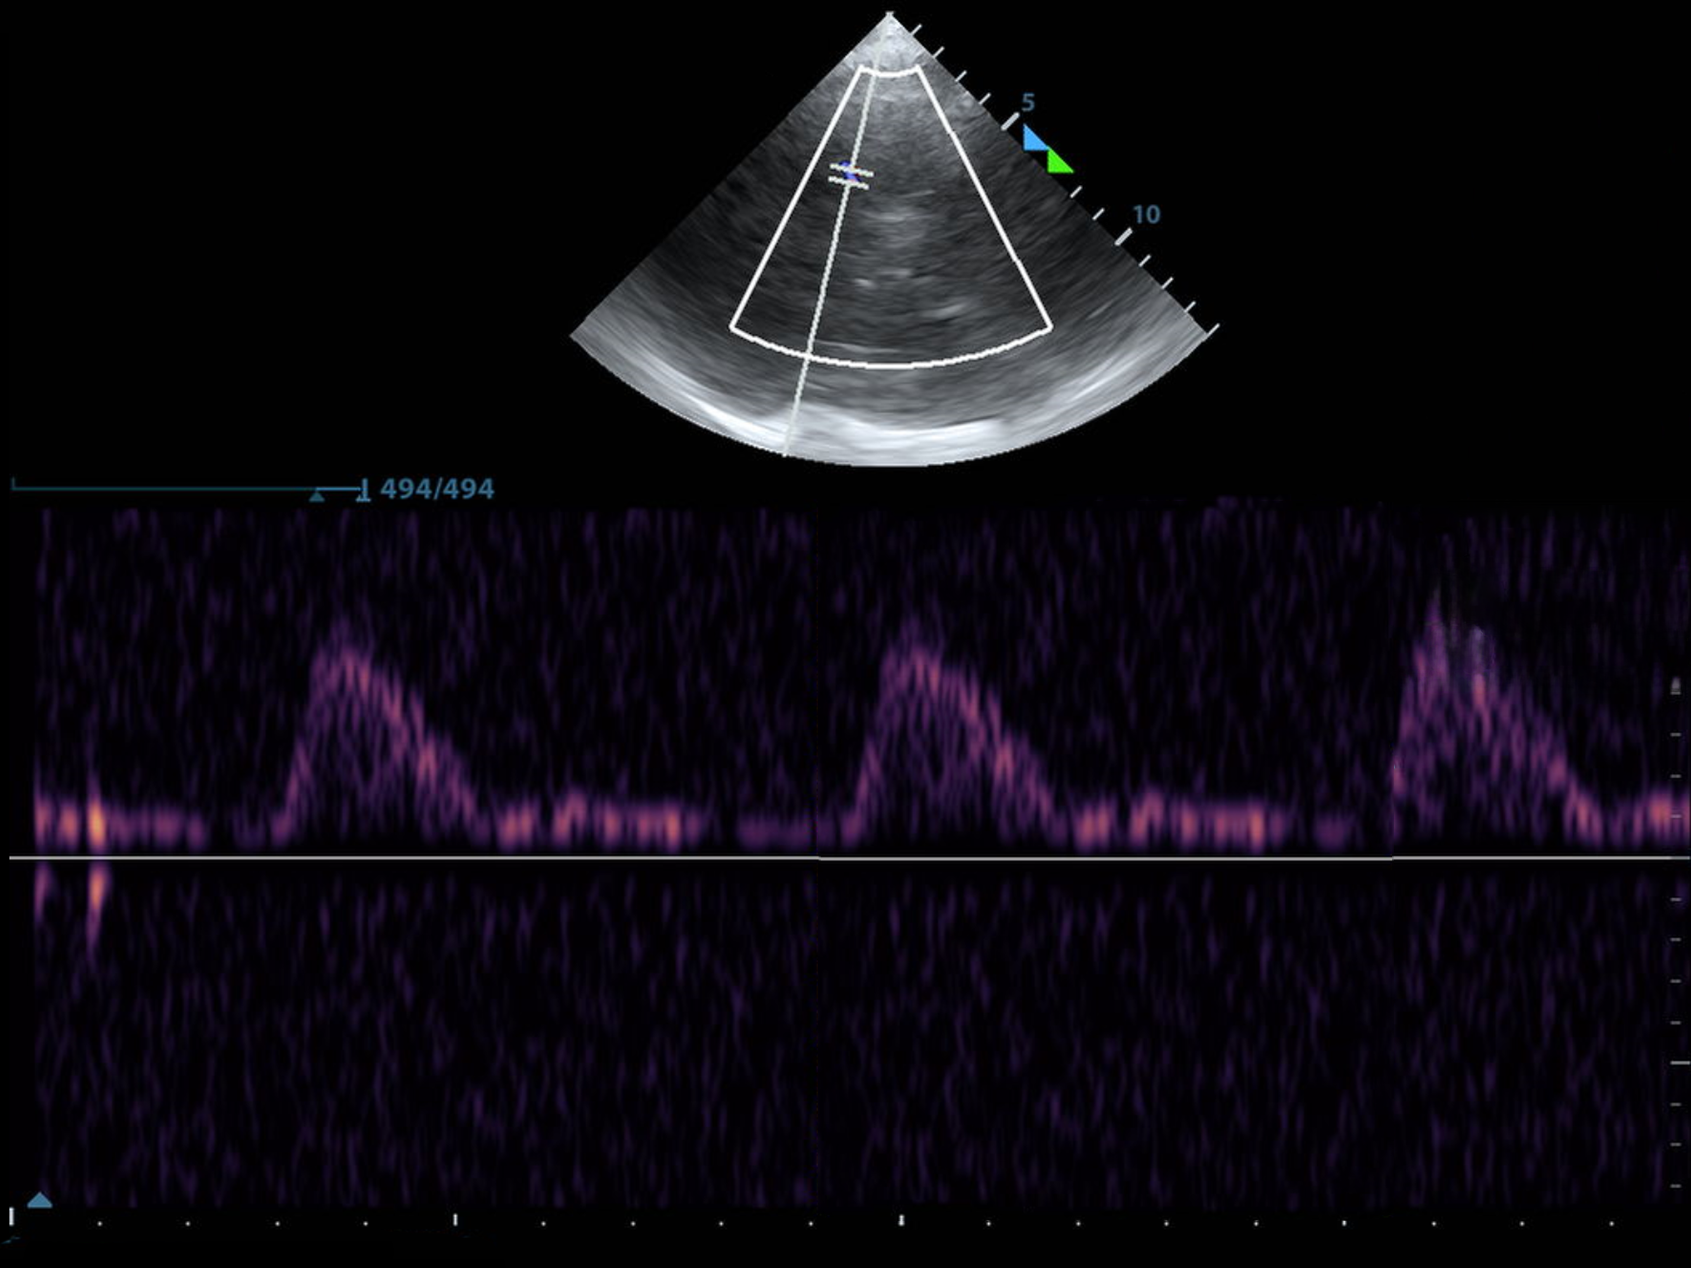

Below, you'll find a normal MCA PI. It's also majestic, virile, ruggedly-handsome, and mine.

As always, I found the MCA with color doppler and put the pulse wave doppler gate on the proximal MCA.

I selected "AutoTrace" and dragged the line from the beginning of the systolic upstroke until end diastole and the machine calculated the rest.

You can also trace the waveform with a cursor, or some machines trace it and provide the calculations without you even asking!